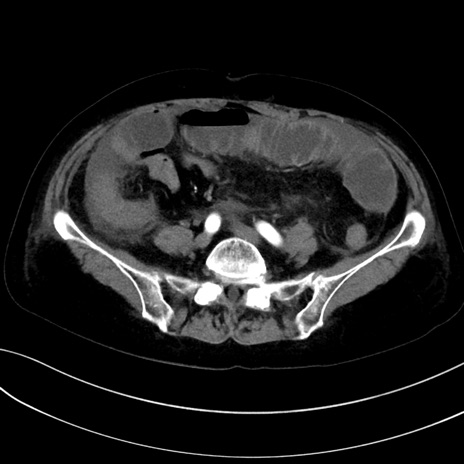

症例13 CT(横断像)1日半後